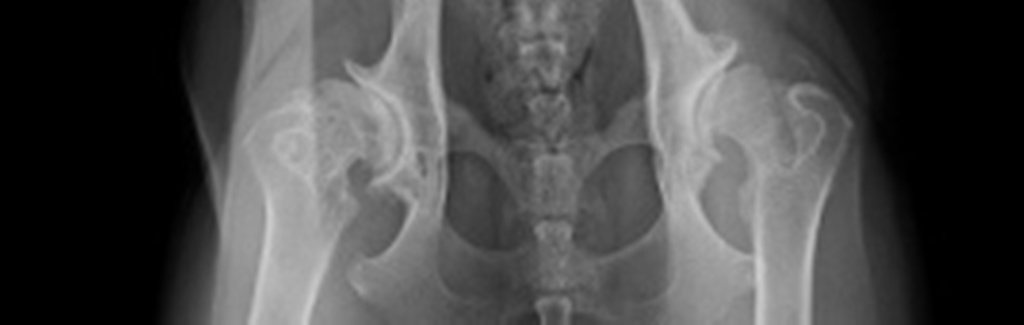

HD-Röntgen:

Bis heute stellt das Röntgen das zuverlässigste und zugleich praktikabelste Verfahren zur Diagnose der HD dar. Andere Methoden wie beispielweise die Ultraschall,- CT- und MRT-Diagnostik sind derzeit für die HD-Diagnostik noch nicht standardisiert oder nicht praktikabel.

Das HD-Röntgen erfolgt durch zwei Personen, die jeweils an den Vordergliedmaßen und Hintergliedmaßen positioniert sind. Es sind zur Zeit zwei Standardlagerungen bzw. Röntgenaufnahmen für die Röntgendiagnostik etabliert und vorgeschrieben. Dies ermöglicht eine einheitliche Interpretation und Begutachtung.

Die Aufnahme in gestreckter Haltung wird für gewöhnlich als HD-Aufnahme verlangt. Der Hund wird auf dem Rücken symmetrisch gelagert, die Gliedmaße gestreckt sowie die Kniegelenke eingedreht. Mit dieser Art von „Stressaufnahme“ können einerseits etwaige Lockerheiten der Hüftgelenke erkannt werden, andererseits ermöglicht das Eindrehen der Kniegelenke die Darstellung des überwiegenden Teils des Oberschenkelhalses.

Voraussetzung für ein objektiv auswertbares Röntgenbild ist eine korrekte Lagerung des Hundes sowie eine optimale Röntgentechnik. Hierzu bedarf es auch einer gewissen Routine, Erfahrung und Kenntnis des röntgenden Tierarztes.

Jede nicht korrekte Positionierung kann zu einer Veränderung der Hüftgelenkssituation führen und erschwert eine objektive Beurteilung. Eine fehlerhafte Lagerung kann auch hier durchaus zu einer Aufnahme führen, die das Gelenk schlechter aussehen lässt, als es in Wirklichkeit ist. In solchen Fällen ist zu entscheiden, ob die vorliegende Aufnahme eine objektive Beurteilung noch zulässt. Die Technik und Lagerung sollte daher mindestens ausreichend sein.

HD-Bewertung:

Um eine möglichste einheitliche Bewertung zu gewährleisten, wurden mehrere Klassifizierungsschemata entworfen. Die Beurteilung erfolgt anhand klar definierter anatomischer Stellen (Kriterien) am Hüftgelenk. Die Befunde werden je nach Schwere in verschiedene Stufen eingeteilt und bestimmen den HD-Grad der Hüftgelenke.

Ein wesentliches Auswertungskriterium ist der Norberg-Winkel. Er ist als der Winkel definiert, der zwischen der Verbindungslinie der Zentren der beiden Oberschenkelköpfe und dem vorderen Pfannenrand abgetragen wird (siehe Abbildung). Bei einem HD-freien Tier sollte er mehr als 105° betragen. Weitere Beurteilungskriterien sind die Kongruenz (Übereinstimmung) von Oberschenkelkopf und Gelenkpfanne, die Weite des Gelenkspaltes, die Pfannenkontur, die Kontur des Oberschenkelkopfes sowie das Vorhandensein von Hinweisen auf arthrotische Prozesse wie walzenförmige Verdickungen des Oberschenkelhalses, Randwülste an der Gelenkpfanne, unter dem Knorpel befindliche Verdichtungen der Knochensubstanz im Pfannenbereich und die Anlagerung von Knochenmaterial am Ansatz der Gelenkkapsel der sogenannten Morgan-Linie.